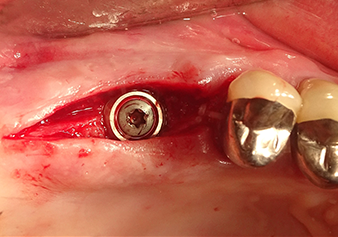

Une patiente de 49 ans, non fumeuse et sans antécédents médicaux remarquables, a été orientée vers notre cabinet de chirurgie orale pour l’extraction chirurgicale de la dent 16 préalable à la pose d’un implant. Après l’extraction, la patiente a rencontré de légers problèmes de sinusite, à la suite de quoi nous avons commencé par attendre six mois avant de prendre la mesure. À l’endroit prévu pour la pose de l’implant, l’os résiduel mesurait 3-4 mm de haut (Fig. 1 et 2).

Après la préparation atraumatique du lambeau muco-périosté, la position de l'implant est marquée à l'aide de l’insert I1 et le site préparé - jusqu’à la perception d’une résistance initiale. Les inserts de piézochirurgie sont utilisés suivant un mouvement ascendant et descendant, sans exercer aucune pression. La vibration piézoélectrique produit l’effet de cavitation souhaité, qui s’avère efficace.

L’insert I2A (diamètre 2,0 mm) est ensuite utilisé pour perforer le plancher sinusien par intermittence et à la plus petite échelle possible. Cette méthode piézochirurgicale spéciale garantit que la membrane de Schneider n’est pas endommagée. Quand le Z25P est utilisé, la membrane est déjà légèrement relevée sous l’effet du fluide de refroidissement délivré via la pointe de l’insert (Fig. 3). Seulement 50 % du fluide de refroidissement sont éjectés afin d'éviter une pression élevée sur le site implantaire.